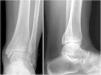

Study variablesThe initial X-rays of all the patients were reviewed, determining the type of fracture according to the Lauge-Hansen classification, and the size of the posterior malleolus was measured in millimetres. The patients were divided into three categories according to the percentage of involvement of the joint surface of the tibia: involvement <10% (group A), between 10% and 25% (group B) and >25% (group C) (Fig. 1). Joint reduction after osteosynthesis was checked in all the patients, measuring the medial clear space and the tibiofibular overlap, assuming an adequate reduction when these were less than 5mm and greater than 10mm respectively.14

After a mean follow-up period of 33 months (12–73 months) after the fracture, all the patients were reassessed in the trauma clinic, where scores of the VAS scales at rest and during exercise were taken (from 0 no pain, to 10 the worst pain imaginable) of the American Orthopaedic Foot and Ankle Society (AOFAS) for the ankle and hindfoot (0–100) and of SF-36 as a general health questionnaire. Weight-bearing X-rays were also taken (AP and lateral) to determine the degree of tibioastragaline osteoarthritis; these were all assessed by the same surgeon using the osteoarthritis classifications of Takakura15 and Van Dijk16,17 (Fig. 2).

We classified the patients into three groups according to joint involvement, and we found that in more than half (55.56%) between 10% and 25% of the joint surface was compromised (group B); 26.67% showed less than 10% involvement (group A), and the remaining 17.78% were included within group C, with more than 25% of the joint surface compromised. Only two of our patients underwent CT scans to assess the fracture, and in both cases we found 50% underestimation of the posterior fragment. The ankle fractures of all of the patients were operated, and no case underwent direct reduction using a posterior approach to the ankle. In 4 of the 8 patients that comprised group C, osteosynthesis of the posterior malleolus was performed with a percutaneous cannulated screw in an anteroposterior direction. We checked that all the cases met the post-surgical joint reduction criteria, with a clear medial space of less than 4mm and a tibiofibular overlap of more than 5mm.14